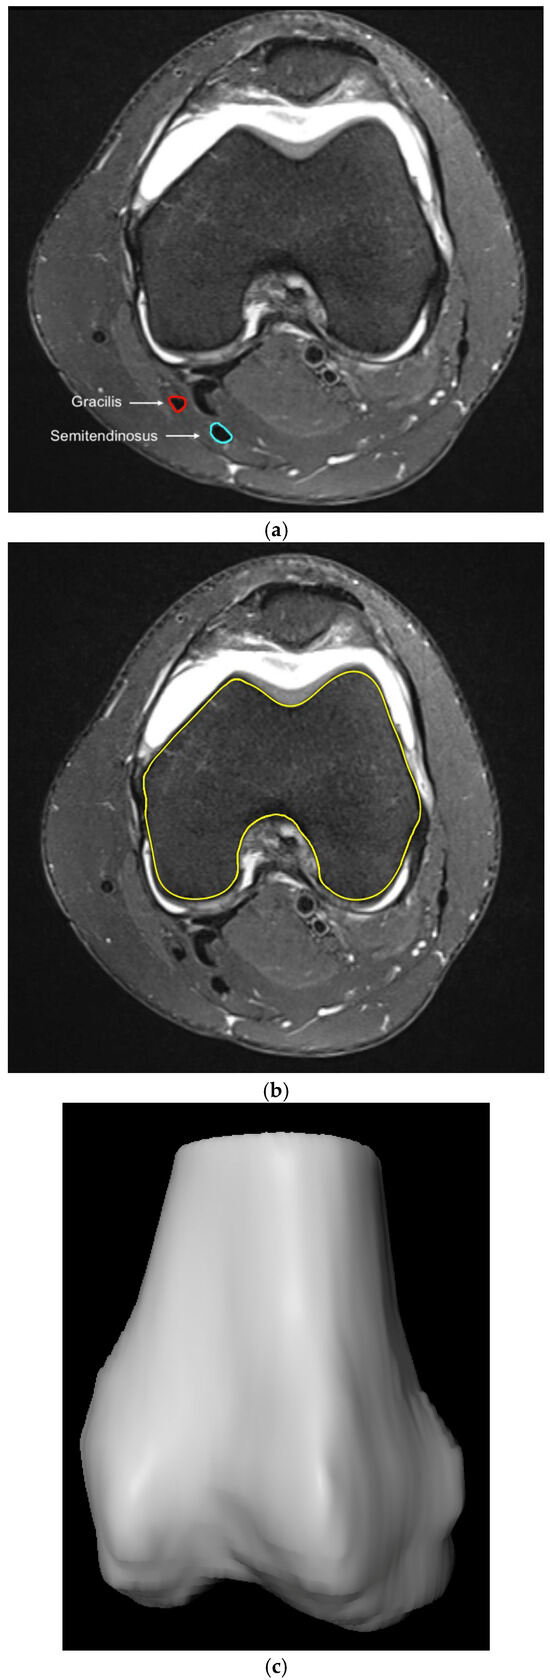

2.2. Methodological Approach